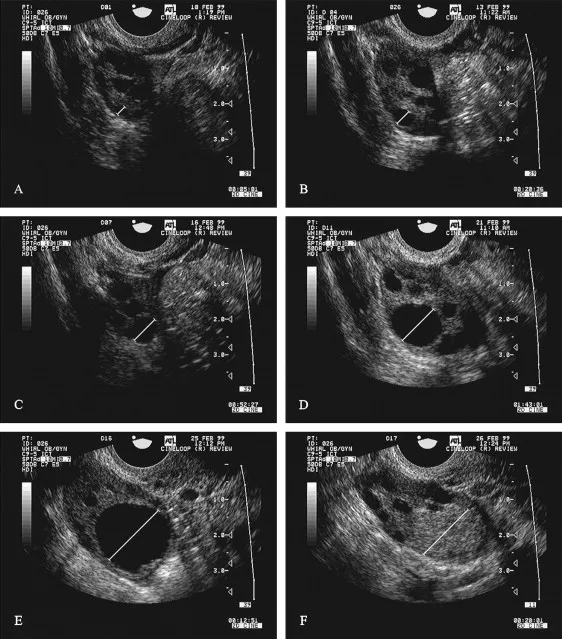

The dominant follicle emerges through superior FSH sensitivity and enhanced aromatase activity. By cycle day 8-10, the leading follicle reaches 10-12 mm diameter and begins producing significant estradiol (>100 pg/mL). This estradiol surge suppresses FSH through negative feedback, starving competing follicles and ensuring single ovulation.

| Follicle Stage | Size (mm) | Duration (Days) | FSH Requirement | Key Features | Atresia Rate (%) |

|---|---|---|---|---|---|

| Primordial | 0.03 | Dormant | None | Single oocyte layer | 99.9 |

| Primary | 0.04-0.2 | 85 | Low | Cuboidal granulosa | 95 |

| Secondary | 0.2-2 | 70 | Moderate | Antral formation | 90 |

| Early Antral | 2-5 | 25 | High | Multiple antra | 85 |

| Dominant | 5-20 | 14 | Variable | LH receptors | 0-20 |